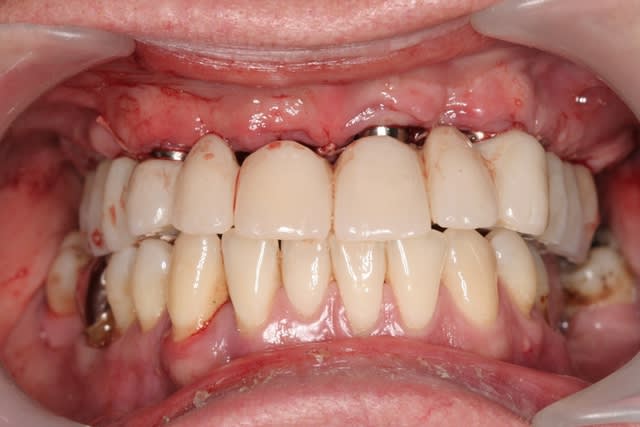

pour les piliers, oui c'était un peu prévisible avec le provisoire où on privilégie l'accessibilité pour l'hygiène...mais l'intervention est toute fraiche et la gencive a en général tendance à remonter le long des piliers

remarque: pas de sourire gingival...donc çà ne se voit pas...

revenons en plutôt au sujet: une MCI, une patiente, et voilà la cicat à 3jours car je viens de la revoir avant ma semaine de congés (pas de pb, s'il y a quoi que ce soit elle a mon n° de portable...)

j'ai remis la photo juste post chir que vous jugiez vous même du repositionnement de la gencive qui est en train de se faire...;-)

je pense que çà va être bien joli pour le définitif...;-)